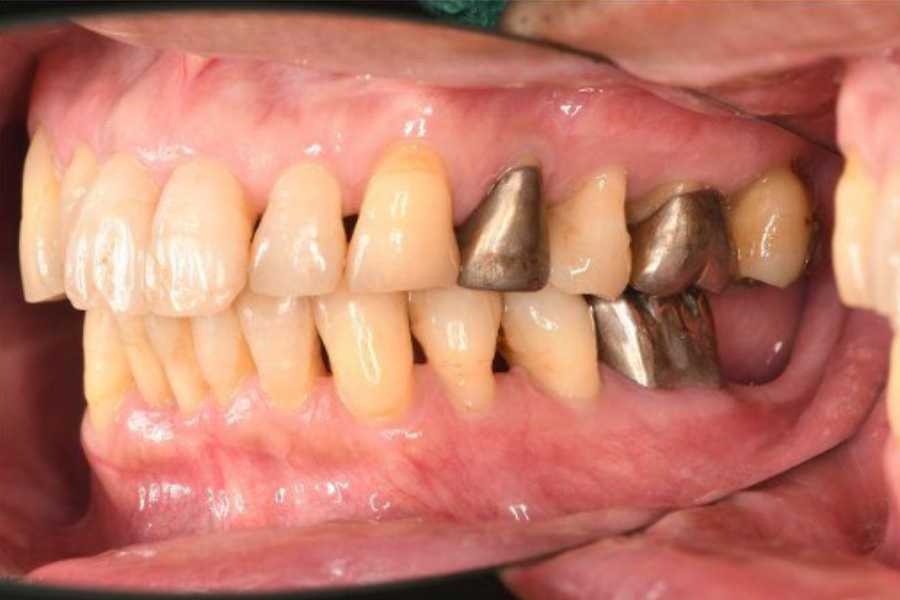

治療前

| 治療内容 | 全顎治療:歯周病治療、抜歯、根管治療、 咬合治療・矯正治療、フルメタルクラウン(保険) |